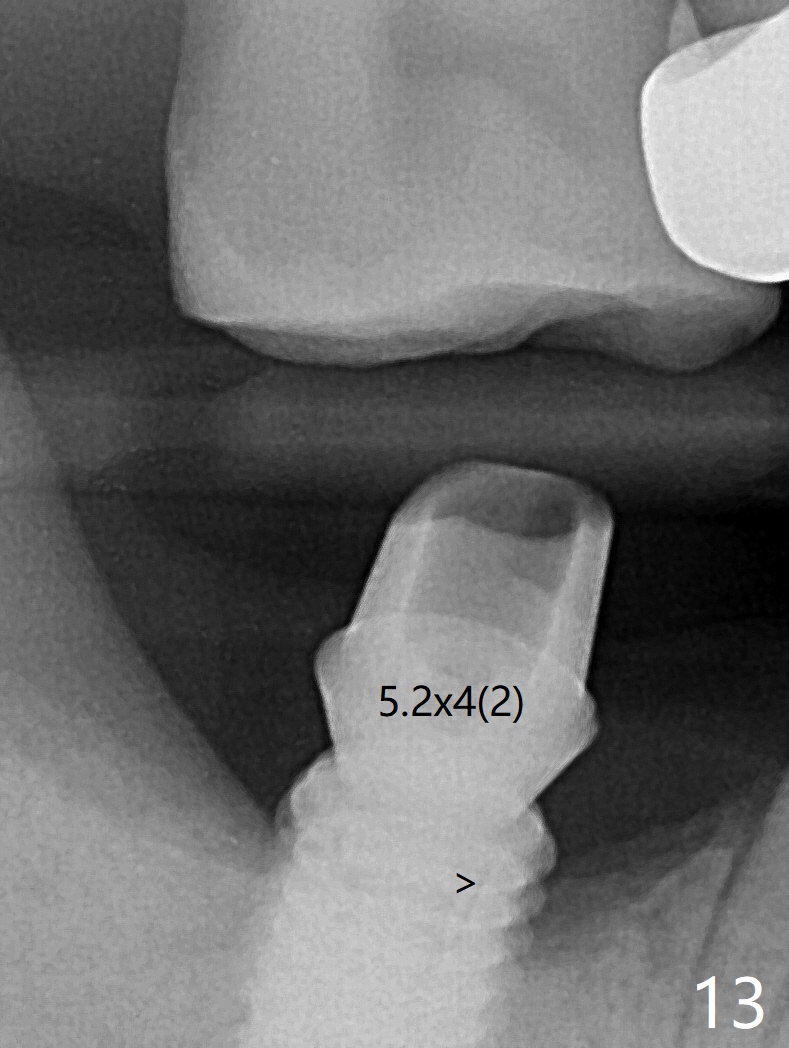

The residual roots of the tooth #31 are lower buccal (Fig.1 B), which in fact is molded and worn by the supraerupted tooth #2. When the tooth is extracted (Fig.2) and an implant, abutment (Fig.3 gold colored) and allograft (*) are placed, the abutment has to be trimmed. An atypical immediate provisional is fabricated by spreading setting acrylic over the abutment and bone graft (Fig.4 P) with occlusal equilibrium. Advantages of the guided surgery are good position (Fig.3 buccolingual), trajectory and depth (Fig.5,6) of the implant. The buccodistally exposed implant threads are packed with allograft in sufficient amount (Fig.3,5,6 *). The atypical immediate provisional breaks down and dislodges 3 weeks postop (Fig.7). In fact the implant plateau is exposed buccally. A monojet is given to the patient for self cleansing. He is instructed to return in 3 weeks. The exposed implant threads are covered 1.5 months postop (Fig.8). Incomplete abutment seating (Fig.9 <) was not noted until 1 year 3 month post cementation when the crown was mobile (Fig.10). A 6x3 mm healing abutment is placed. Three days later, the crown is sectioned and separated from the abutment. The latter returns to place; due to angulation associated with PA, the gap between the implant and abutment is indistinct (Fig.11). Bitewing is taken; the gap exists (Fig.12 <). The abutment seems to be seated deep; there is apparently soft tissue interference. A 5.2x4(2) mm abutment remains incompletely seated (Fig.13 >). A 5.2x4(3) mm one is completely seated (Fig.14 <). Zirconium crown with an access hole is cemented in the mouth. The crown and abutment is then removed for residual cement removal and reseated and torqued (Fig.15). Four months later, the Zirconium crown is fractured (Fig.16). Impression is retaken for high noble metal crown without access hole for strength (Fig.17).